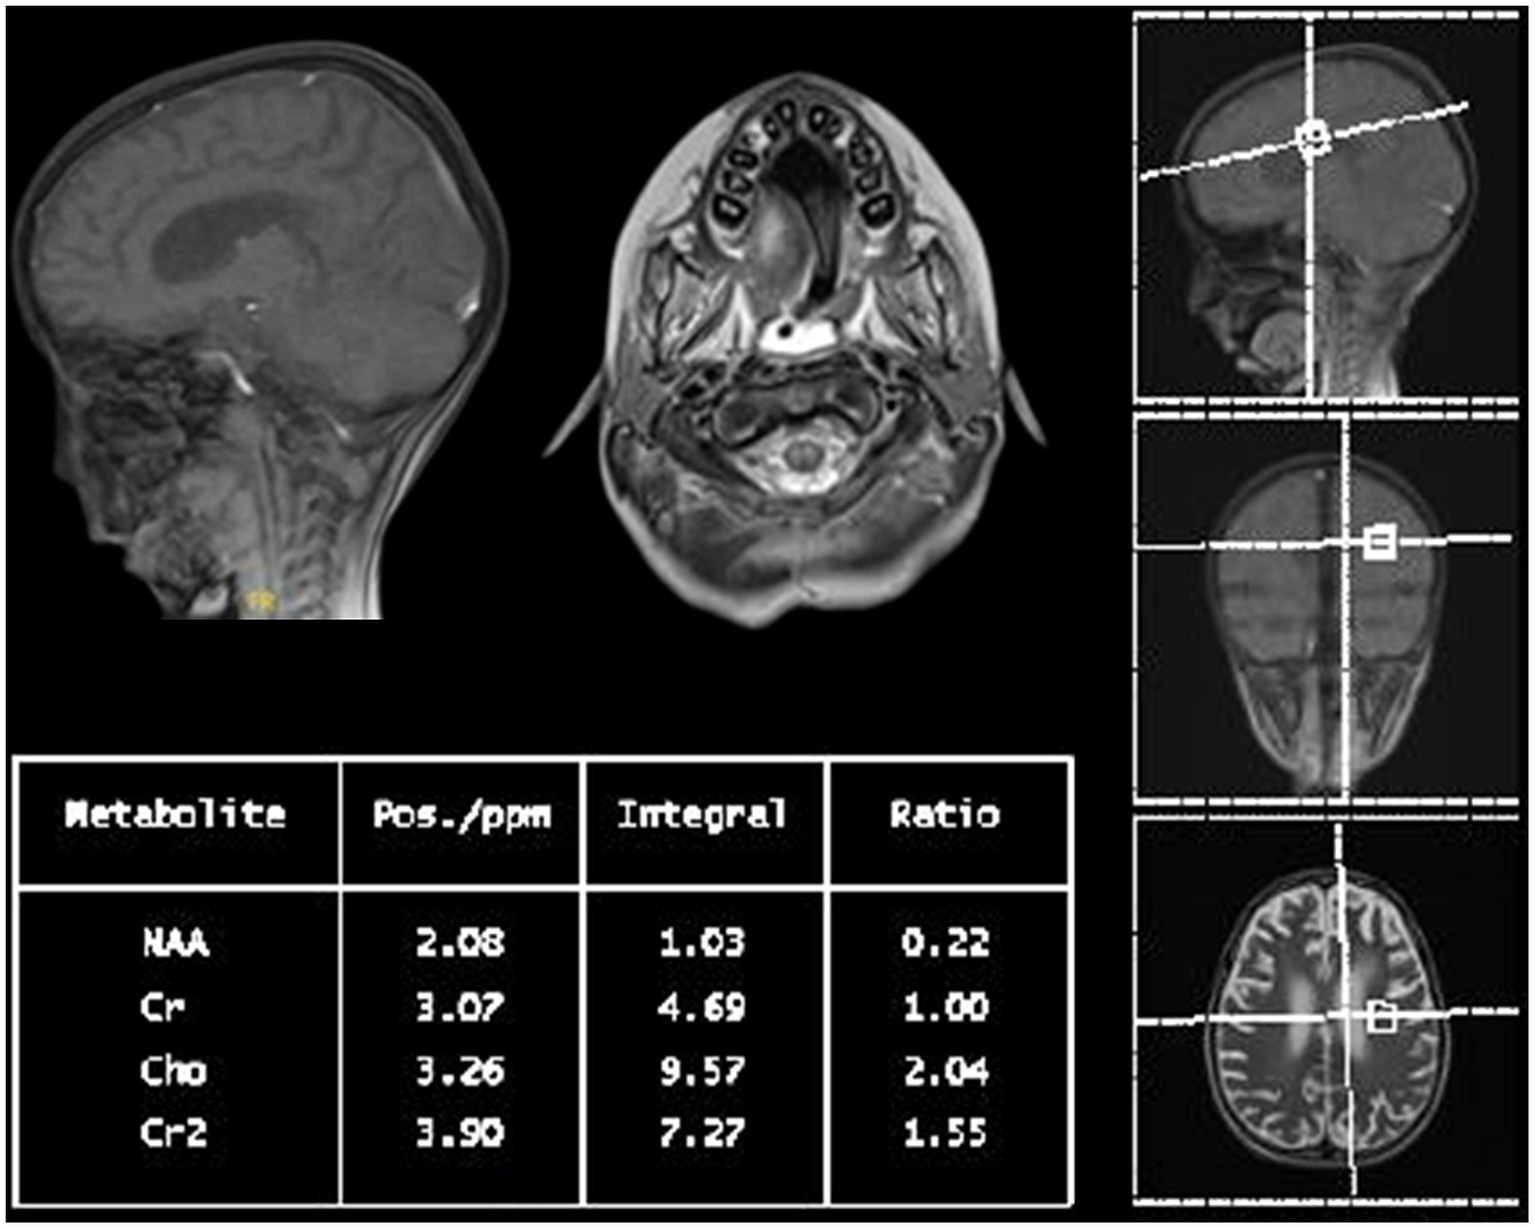

Within a month, the patient’s GCS significantly deteriorated to 3/15. Pupils were fixed and dilated at 6 mm, the gag reflex disappeared, and the corneal reflex exhibited minimal response. Clonus, which was previously present, was now absent. WES results returned negative, revealing no clinically relevant variants related to the described phenotype. This ruled out the differential diagnosis of progressive myoclonic epilepsy as well as other potential metabolic or mitochondrial diseases that could account for the patient’s symptoms. Two weeks later, with no improvement and the absence of the corneal reflex, a buccal swab sample was sent for whole genome sequencing (WGS). No further escalation of immune therapy occurred, and only symptomatic treatment for seizures was provided. Brain MRI indicated further worsening of the diffuse brain parenchymal atrophy with resultant ventricular enlargement while spinal MRI revealed abnormal diffuse T2 signal intensities involving the central and anterior cord extending down to the conus medullaris (see Figures 1E,F). Brain multi-voxel MR spectroscopy findings were further suggestive of an inflammatory or demyelinating process post-COVID-19 infection (see Figure 2).

Figure 2

Multi-voxel MR spectroscopy of the patient: short and long TE at the basal ganglia, peritrigonal white matter, and cerebellar peduncles with increased choline to creatinine ratio and a decreased N-acetylaspartate to creatine ratio suggest an underlying inflammatory or demyelinating process.